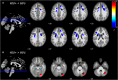

Results: The DBM analysis revealed decreased values (i.e., tissue atrophy) in the bilateral frontal regions in the HIV+ group, including bilateral superior frontal gyrus, left middle frontal gyrus, and their neighboring white matter tract, superior corona radiata. The functional connectivity between the right superior frontal gyrus and the right inferior temporal region was enhanced in the HIV+ group, the connectivity strength of which was significantly correlated with the global deficit scores (r = 0.214, P = 0.034), and deficits in learning (r = 0.246, P = 0.014) and recall (r = 0.218, P = 0.031). Increased DBM indexes (i.e., tissue enlargement) of the right cerebellum were also observed in the HIV+ group.